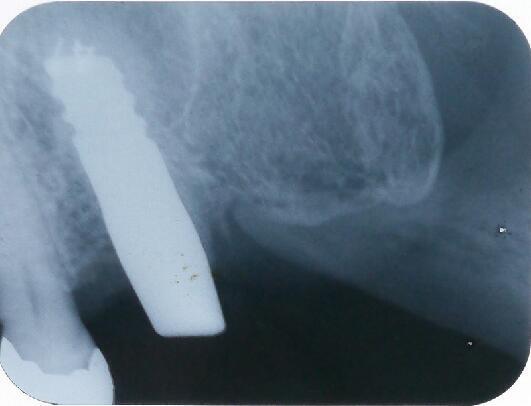

4ヵ月後のエックス線写真です すでに骨が出来ております

その後かぶせ物をして定期検診へ移行します